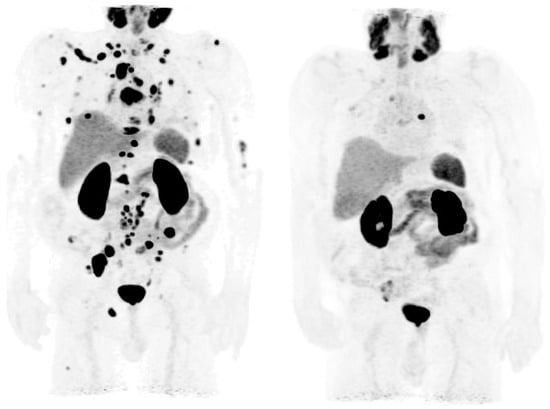

3.3. Evaluation of PCa Patients for Possibility of PSMA Radioligand Therapies

- Grubmuller, B.; Senn, D.; Kramer, G.; Baltzer, P.; D’Andrea, D.; Grubmuller, K.H.; Mitterhauser, M.; Eidherr, H.; Haug, A.R.; Wadsak, W.; et al. Response assessment using 68Ga-PSMA ligand PET in patients undergoing 177Lu-PSMA radioligand therapy for metastatic castration-resistant prostate cancer. Eur. J. Nucl. Med. Mol. Imaging 2019, 46, 1063–1072. [Google Scholar] [CrossRef] [Green Version]

- Grubmuller, B.; Rasul, S.; Baltzer, P.; Fajkovic, H.; D’Andrea, D.; Berndl, F.; Maj-Hes, A.; Grubmuller, K.H.; Mitterhauser, M.; Wadsak, W.; et al. Response assessment using [68Ga] Ga-PSMA ligand PET in patients undergoing systemic therapy for metastatic castration-resistant prostate cancer. Prostate 2020, 80, 74–82. [Google Scholar] [CrossRef]